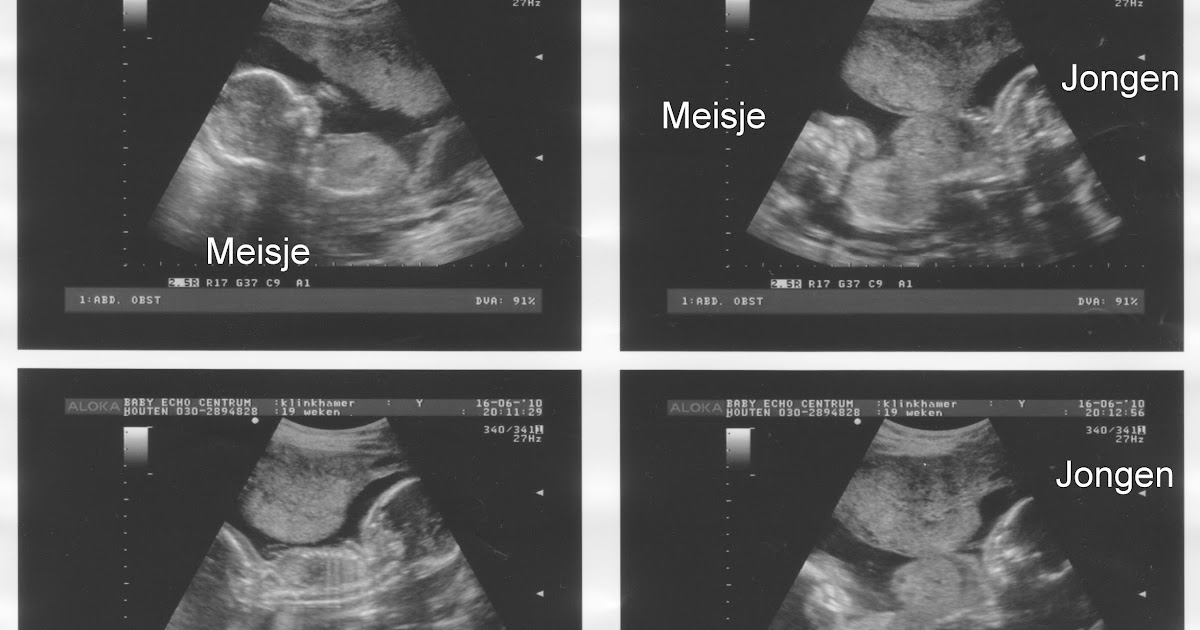

Het gedrag van je kindje kan soms ook een indicator zijn Jongen of meisje? Hoe zit het precies met of je een jongetje of een meisje krijgt? Bij sommige foto's staat er een pijltje bij of staat het bijgeschreven.

Echo jongen of meisje? 1 24baby Forum. Geslacht: jongen Bij jongens staat de nub in een hoek van 30 graden omhoog Wordt het een meisje of een jongen? Daar ben je waarschijnlijk ook heel nieuwsgierig naar

Pret Echoscopie Verloskundige Praktijk Meerssen. Wil je hier eerst meer over weten kijk dan op echo jongen, echo meisje, geslachtsbepaling 13 weken , echo geslacht herkennen, geslacht baby en Jongen of meisje? Hoe kan jij ontdekken of het een jongen of meisje is? Veel mensen horen bij de 20-wekenecho wat het geslacht is, of wagen zelf een gokje met de nub-theorie